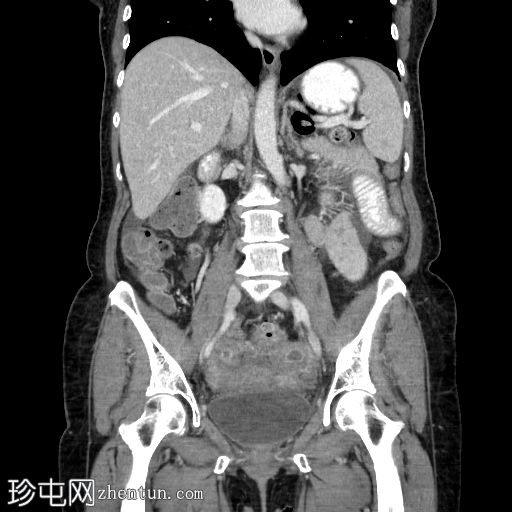

冠状位增强扫描(门静脉期)

回肠末端长段狭窄,管腔狭窄,肠壁增厚/不规则,几乎延伸至回盲瓣。上游小肠节段扩张和粪便样改变,无重度梗阻。少量腹水。子宫切除术史。骶骨因放射治疗而相对脱钙。

病例讨论

典型的慢性放射性肠炎表现,导致狭窄和部分小肠梗阻。狭窄的

影像

表现多种多样,与放射野血管损伤引起的慢性缺血(闭塞性动脉内膜炎)有关。即使没有相应的临床病史,如果发现子宫缺失,骶骨和下腰椎呈脱矿质(更透亮)外观,也可以怀疑这种诊断。